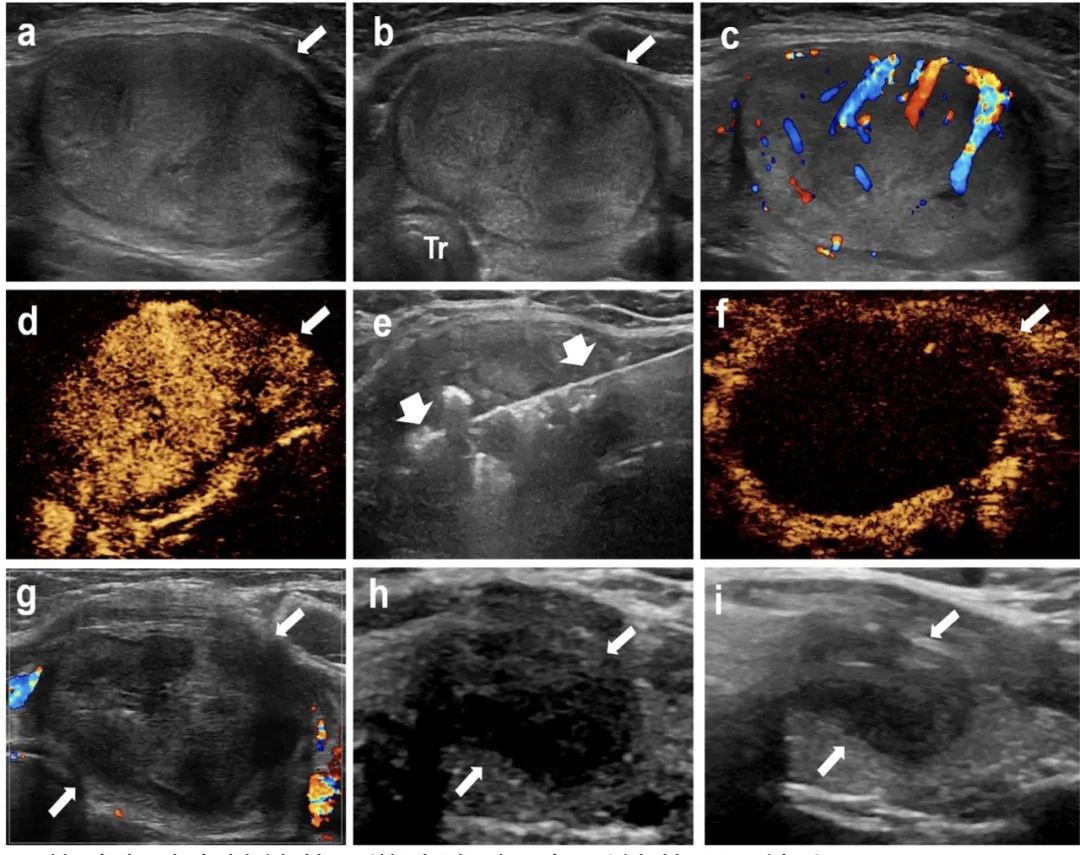

針對該問題,石文媛主任團隊開創(chuàng)性地將微波消融技術應用于兒童良性甲狀腺結節(jié)的治療。連續(xù)分析了2018年1月至2021年12月在北京兒童醫(yī)院接受經皮微波消融治療的有癥狀良性甲狀腺結節(jié)患兒25名,共 34枚結節(jié)。所有患兒均隨訪半年以上(中位隨訪時間12個月,范圍6 - 48個月)。結果顯示:經皮微波消融治療后,結節(jié)體積逐漸減?。ㄎ⒉ㄏ谇爸形惑w積5.86 mL,末次隨訪評估中位體積0.34 mL),末次隨訪評估體積縮小率達到85.03%,技術有效率達91.2%。結節(jié)相關壓迫癥狀、美容相關問題均得到顯著改善。術后一個月隨訪甲狀腺功能維持在正常范圍之內,提示微波消融在滅活甲狀腺結節(jié)的同時不影響正常甲狀腺功能。

甲狀腺左葉實性結節(jié),微波消融4年后結節(jié)明顯縮小